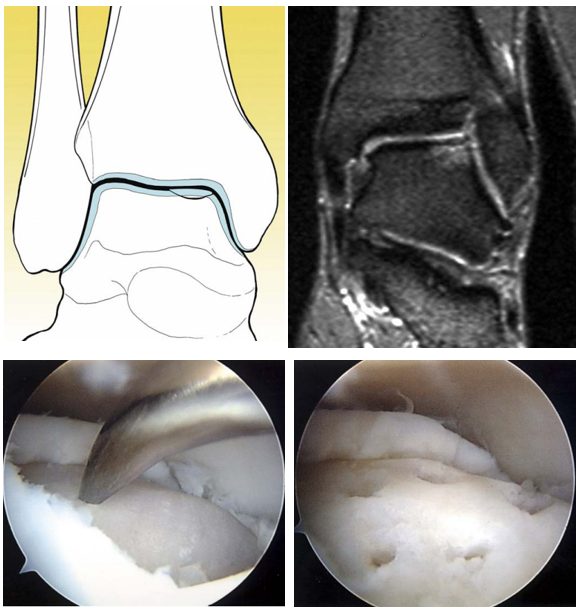

BMS + скаффолд (M-BMS / AMIC)

Дополнение микрофрактуринга биорезорбируемой коллагеновой мембраной для улучшения качества регенерата — аутологичный матрикс-индуцированный хондрогенез (AMIC — Autologous Matrix-Induced Chondrogenesis).

Принцип: мембрана выполняет роль каркаса (scaffold), удерживая кровяной сгусток и мезенхимальные стволовые клетки в зоне дефекта, создавая оптимальное микроокружение для хондрогенной дифференцировки.

Показания: дефект ≥ 1.0 см²

Техника:

- Артроскопический или открытый дебридмент + микрофрактуринг (как описано выше)

- Измерение дефекта

- Вырезание мембраны (Chondro-Gide® — наибольшая доказательная база) по размеру дефекта

- Фиксация мембраны: фибриновый клей (Tisseel®) или резорбируемые швы

- Мембрана укладывается пористым слоем к кости (для адгезии клеток), гладким — к полости сустава

Предпочтительный скаффолд: Chondro-Gide® — двухслойная коллагеновая мембрана I/III типа. [Grade B, Level III — DGOU 2024]

Результаты:

- Выживаемость 84.2-92.1% при среднесрочном/долгосрочном follow-up

- Осложнения: 5%

- Одноэтапная процедура (в отличие от ACI)

- По данным DGOU 2024, результаты M-BMS сопоставимы с ACI при отсутствии донорской морбидности

Рис. 11. Закрытие дефекта коллагеновой мембраной (AMIC)